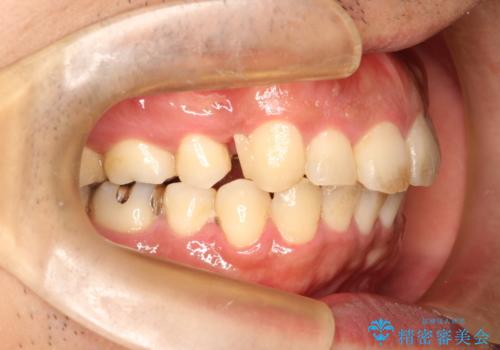

出っ歯の抜歯矯正 裏側ワイヤーによる目立たない矯正

- 出っ歯が気になるとのことで来院されました。

上顎の前から4番目の歯を両側、合計2本抜歯して矯正する計画としました。

目立たない装置がご希望でしたので、上下裏側ワイヤー装置を選択されました。